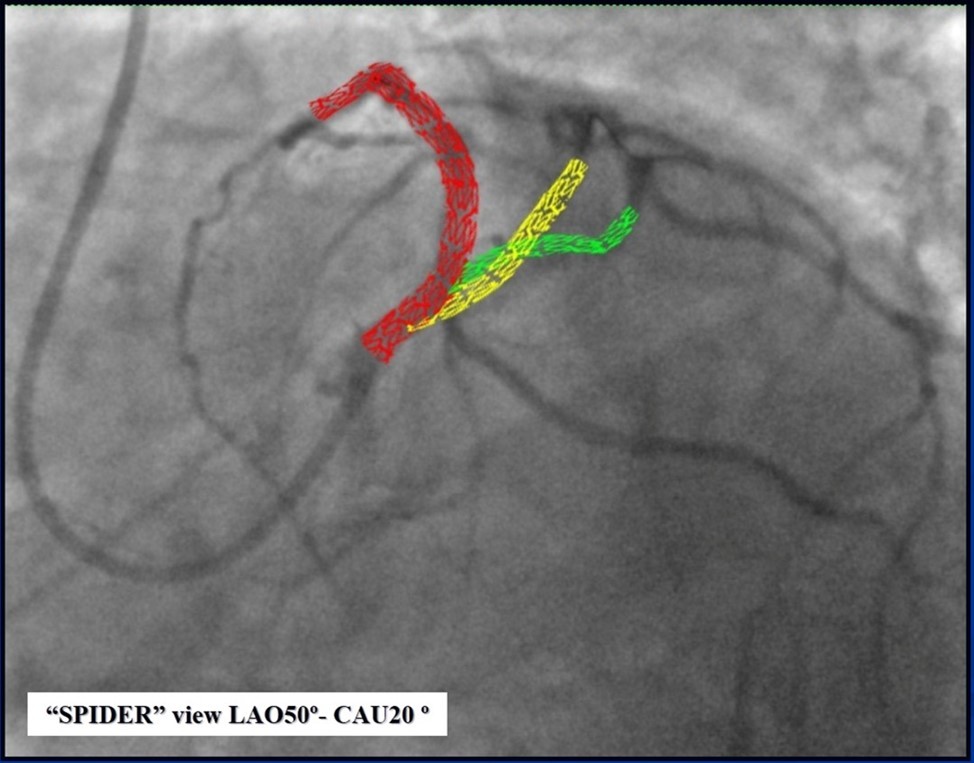

Due to financial problems the second stage was performed after 3 months (during this time the patient solved his financial problems). CAG revealed patent stents in LAD (Figure 7), and 60-70% restenosis by BMS in RCA (Figure 8). In-stent restenosis was treated by plain old balloon angioplasty (POBA), the optimal result was obtained (Figure 9). After LMCA quadrifurcation balloon predilation, 2.5×26 mm DES (Resolute Integrity, Medtronic) was implanted in the IMA, using a modified balloon mini-crush technique. The stent was minimally protruded in the LMCA and its edge was crushed by preloaded MB balloon. Next 2.5×30 mm DES (Resolute Integrity, Medtronic) was implanted in OM1 through the CX (first marginal and circumflex arteries in this particular case have the same ostium). The stent was protruded in the LMCA as in conventional modified balloon crush stenting technique, after stent deployment, its balloon was pulled back and overinflated, then protruded stent was crushed by preloaded MB balloon (Figure 10). 3.5×15 mm DES was implanted in the LMCA so that distal part of the stent covered ostial and proximal segments of the LAD. Sequential post-dilatations were performed using a kissing balloon technique (1. LMCA-LAD-IMA,2. LMCA-LAD-CX-1OM). After post-dilatations, through the stent implanted in CX-OM1, coronary wire and smaller diameter balloon (2.0 mm) were advanced in direction of the CX mid-segment and by balloon dilatation stent’s strut was opened (provisional stenting technique for CX). Finally, the proximal optimization technique was performed in the LMCA using a 3.5 mm diameter non-compliant balloon (Figure 11). The final angiographic image was good, the intervention ended without complications (Figure 11, Figure 12). We could not confirm the result with IVUS or OCT due to several technical and financial problems (not covered by insurance). 1 month after PCI, at regular checkout, the ejection fraction was 48%, the functional class of the Congestive Heart Failure decreased from class II-III to class I and the patient complaints have been disappeared.

Figure 12.Schematic presentation of the implanted stents, “spider” projection.